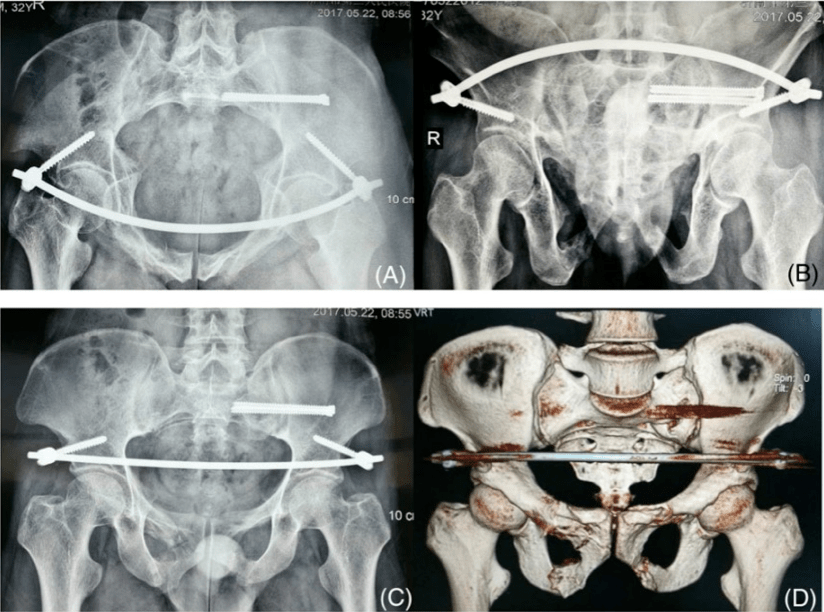

骶骨骨折 骶髂关节脱位 耻骨联合分离 求手术方案 [病例帖]

骨盆三维ct重建后面观,右侧髂骨后部骨折,骶髂关节分离

结论:tirobot辅助经皮骶髂关节置钉及髂前下棘椎弓根置钉是准确且微创